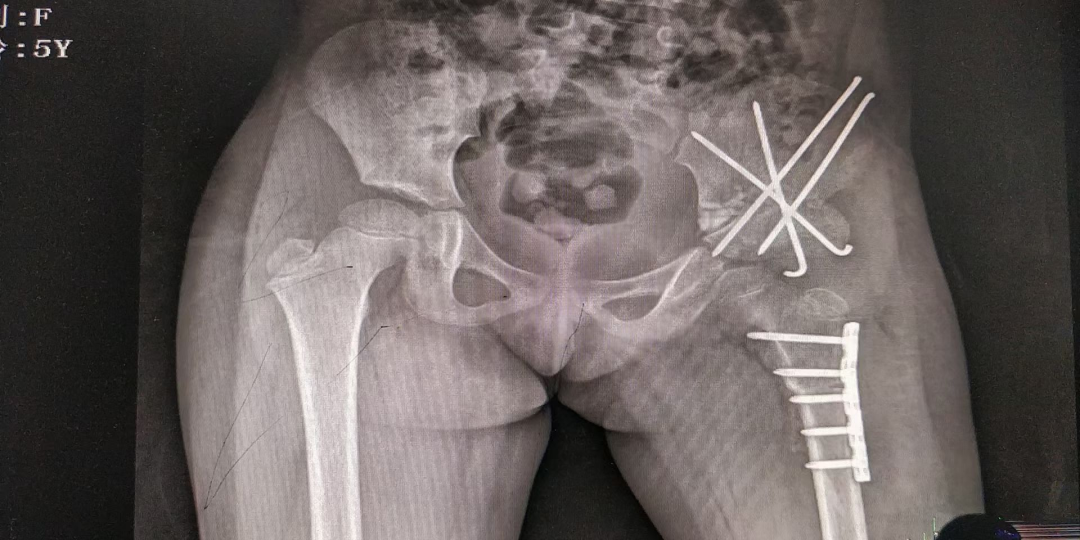

图片图片图片

儿童股骨干骨折闭合复位微创弹性髓内针内固定